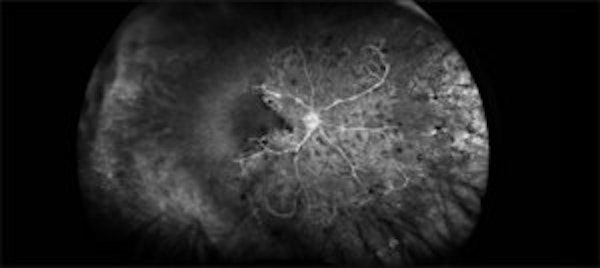

Total Rhegmatogenous retinal detachment with lattice degeneration & Vitreous haemorrhage

72-year male presented PVD induced total retinal detachment with vitreous hemorrhage.